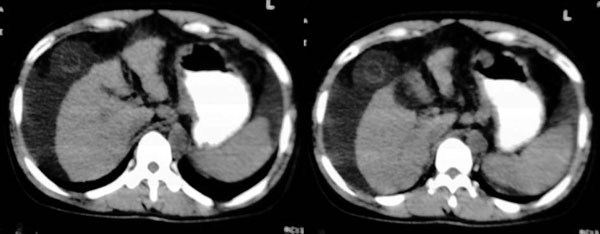

患者:女,43岁,自觉全身肿胀8个多月。b超提示:肝硬化、腹水,胆囊炎。胰、脾、肾未见明显异常。

肝脏形态不正常,比例失调,肝裂增宽,应该是肝硬化、腹水、脾脏稍大。

肝脏体积变小,左右比例失调,右肝变小较剧,脾脏增厚,腹水征象明显考虑肝硬化、腹水

肝脏体积缩小,左右肝比例失调,轮廓不规整,肝裂增宽,肝周见新月形液性密度影,脾脏增厚.应诊断为肝硬化,腹水,脾大.